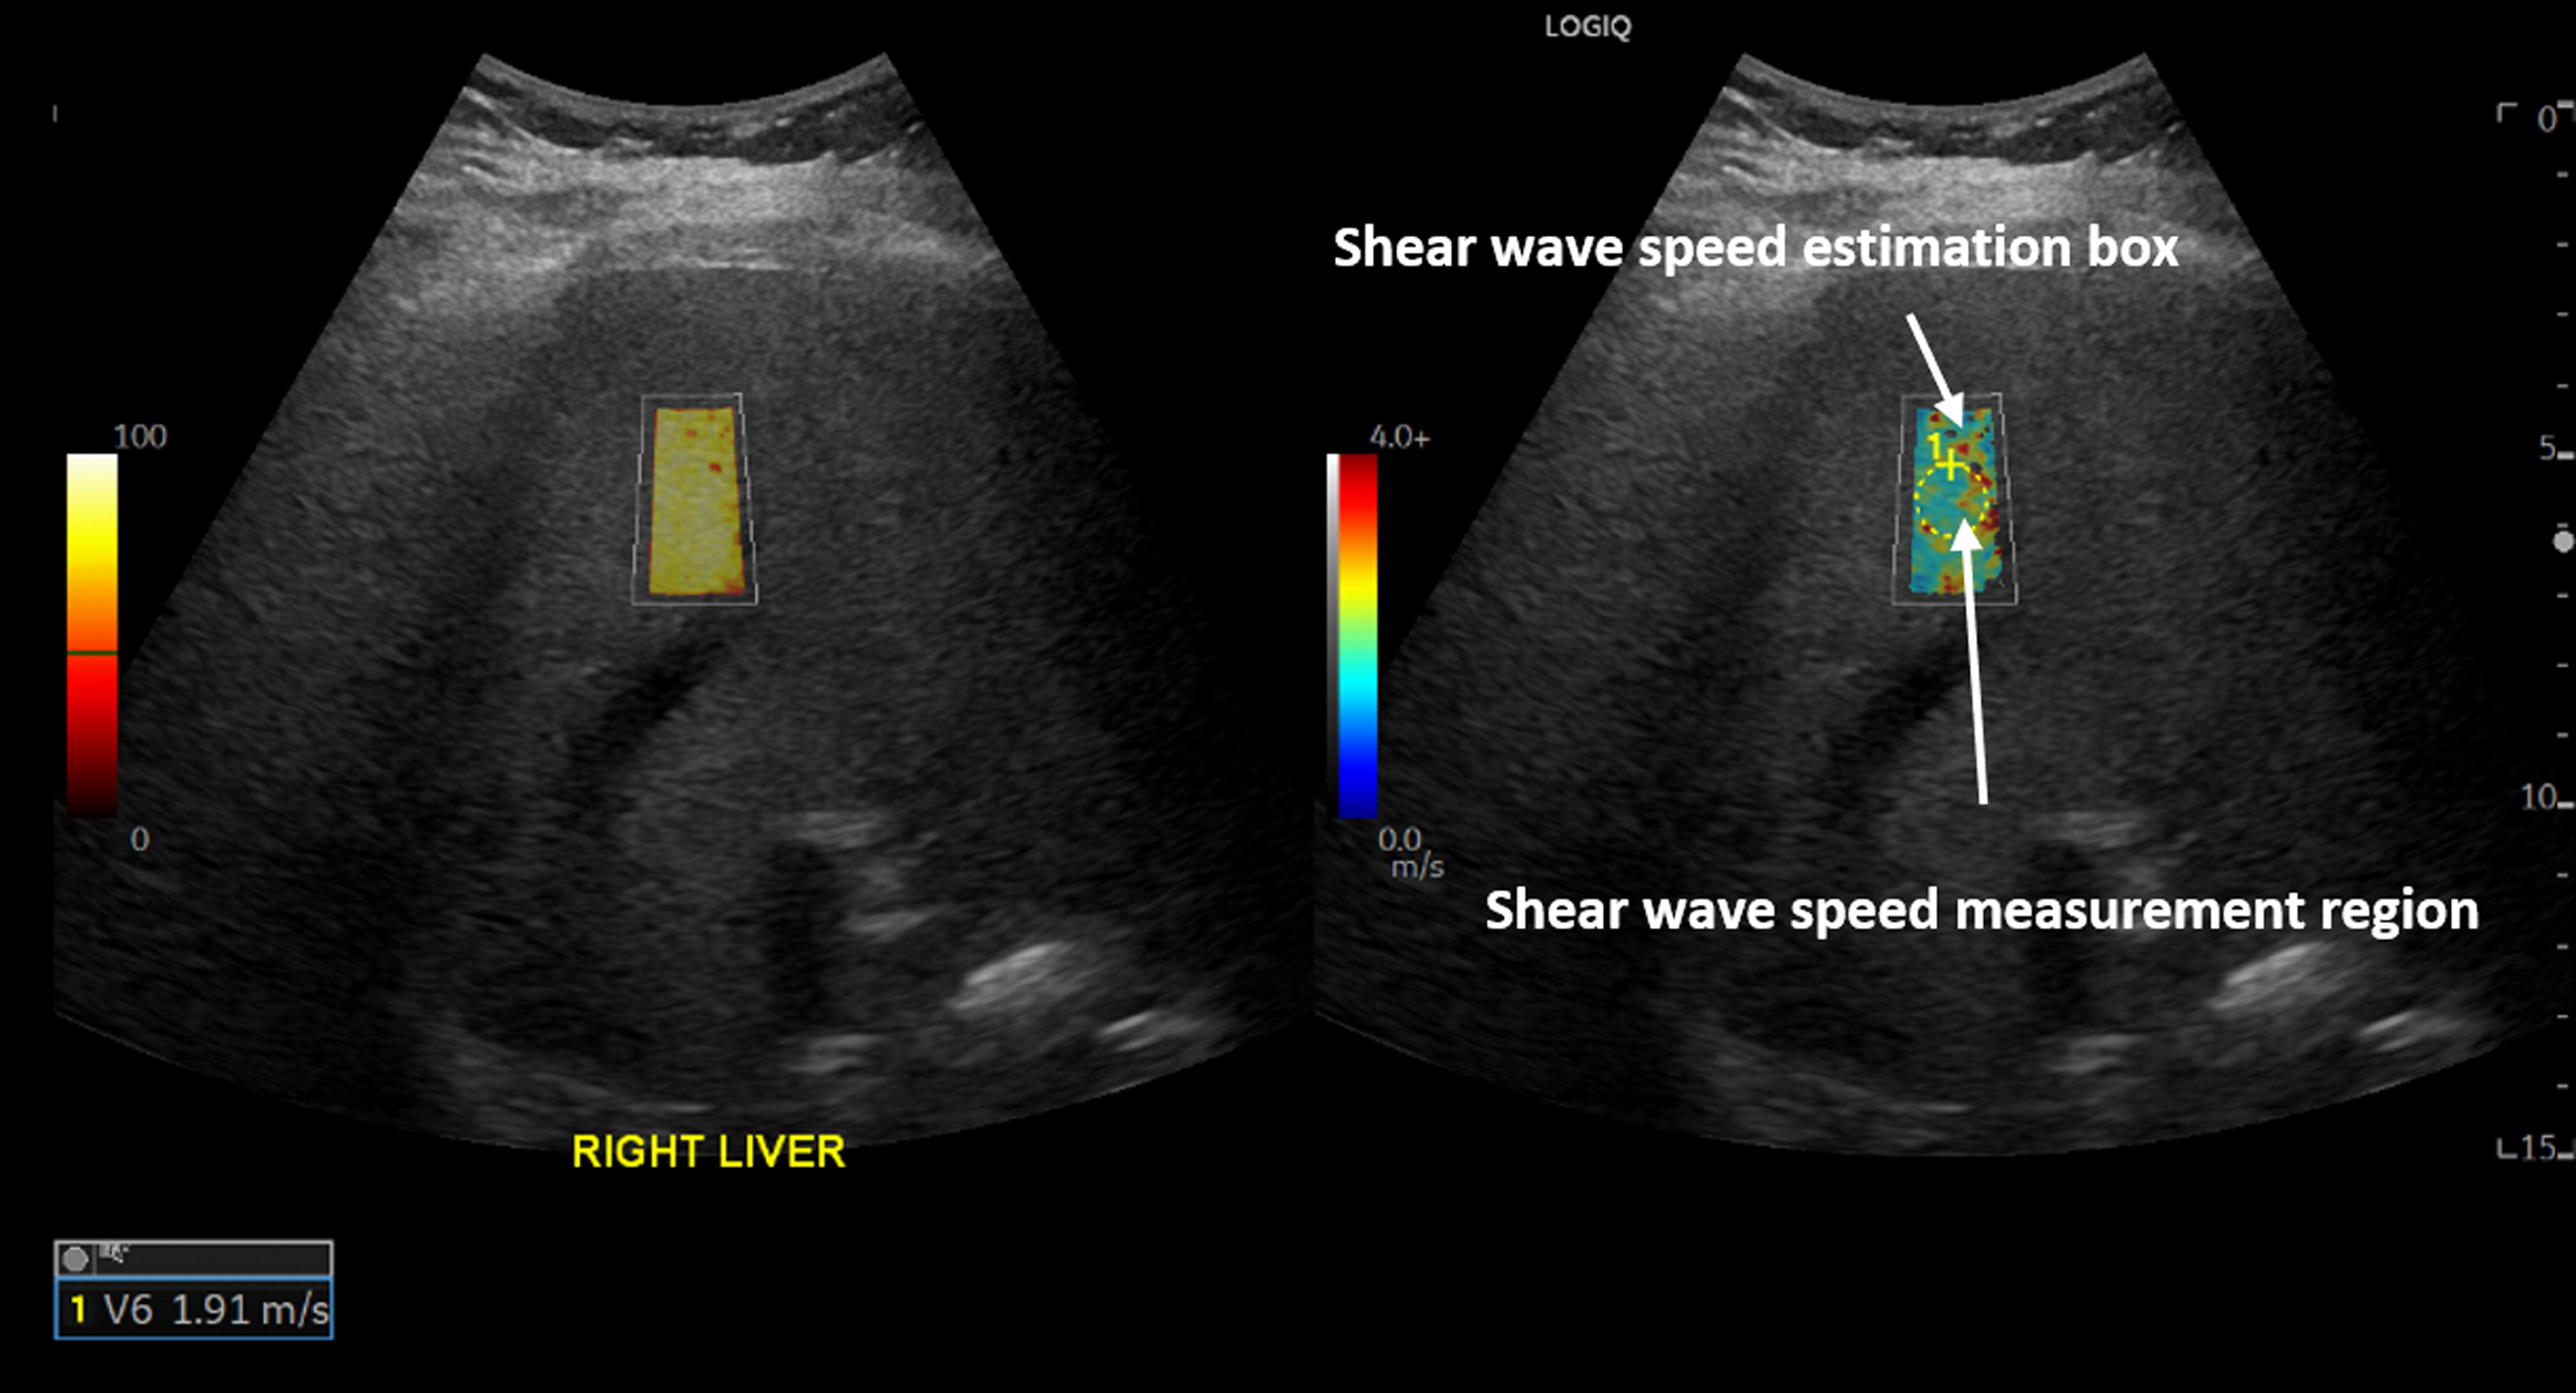

New research with ultrasound shear wave elastography (SWE) suggests that liver stiffness, a marker of fibrosis, increases in patients with a history of COVID-19 infection, according to a study presented at the Radiological Society of North America (RSNA) 2022 Annual Meeting.

Elevated transaminases in patients with COVID-19 suggest the presence of liver injury during acute infection, but whether this liver injury leads to lasting liver damage remains unknown. To identify lasting hepatic injury, Dr. Heidari and colleagues compared liver stiffness on ultrasound SWE in patients with a history of COVID-19 infection to that of healthy controls.

The COVID-19 positive group included 31 patients (mean age 53.1) who had a positive PCR test result at least 12 weeks prior to having ultrasound SWE. Elastography was performed at an average of 44 weeks (12 to 81 weeks) after a positive PCR test result. The pandemic control group was comprised of 50 patients (mean age 55.2) who had ultrasound SWE during the COVID-19 pandemic and had a history of only negative PCR test results. The pre-pandemic control group included 50 patients (mean age 58.2) who had ultrasound SWE before the pandemic. The primary endpoint was the average difference in median Young’s modulus between post-COVID-19 patients and controls after accounting for age, sex and time period.

COVID-19 infection was associated with an average increase in the median Young’s modulus of 1.71 kPa. The COVID-19 positive group had a higher median liver stiffness (7.68 kPa) in comparison to the pandemic control group (5.99 kPa). The pre-pandemic control group had a median liver stiffness of 7.01 kPa.